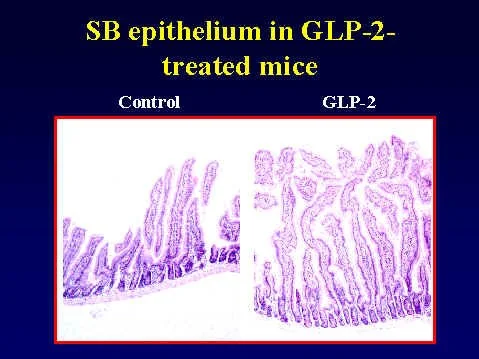

Treatment of rats with insulin reverses the villus hyperplasia (left panel compared to right) and reduces circulating levels of GLP-2 See Intestinal growth is associated with elevated levels of glucagon-like peptide 2 in diabetic rats. Am J Physiol 1997 273: E815-20